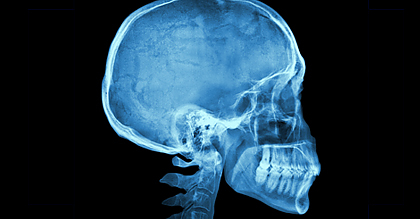

Büki András, a PTE idegsebészeti klinikájának igazgatója, a cikk egyik szerzője kedden áttörésként értékelte a kutatás eredményét. Az idegsebész professzor annak előzményeiről kifejtette: egy év alatt világszerte több mint 50 millió ember szenved koponyasérülést, amelyet jelenleg elsősorban képalkotó eszközökkel diagnosztizálnak. A kutatás eredményeként két biomarkert (GFAP és UCH-L1 elnevezésű fehérjéket) azonosítottak, amelyek kimutatása a vérből és az agyvízből már a korai szakaszban utal a páciens sérülésének súlyosságára.

A kétezer betegen elvégzett vizsgálatok szerint ezeknek a biomarkereknek az együttes vizsgálatával, elsősorban az enyhe és közepesen súlyos koponyasérültek esetében 35 százalékkal csökkenthető a CT-vizsgálatok száma. A kutatás megállapításai nyomán kifejlesztendő új diagnosztikai eszköz páciensek számára sugárdózis-csökkenést, az ellátó intézményeknek pedig költséghatékonyabb működést jelenthet - magyarázta.